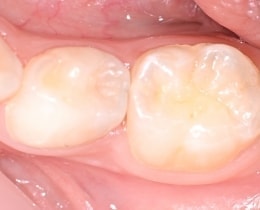

①治療前

お口の中をみただけでは、歯と歯の間に虫歯があるかどうか、わかりにくいです。